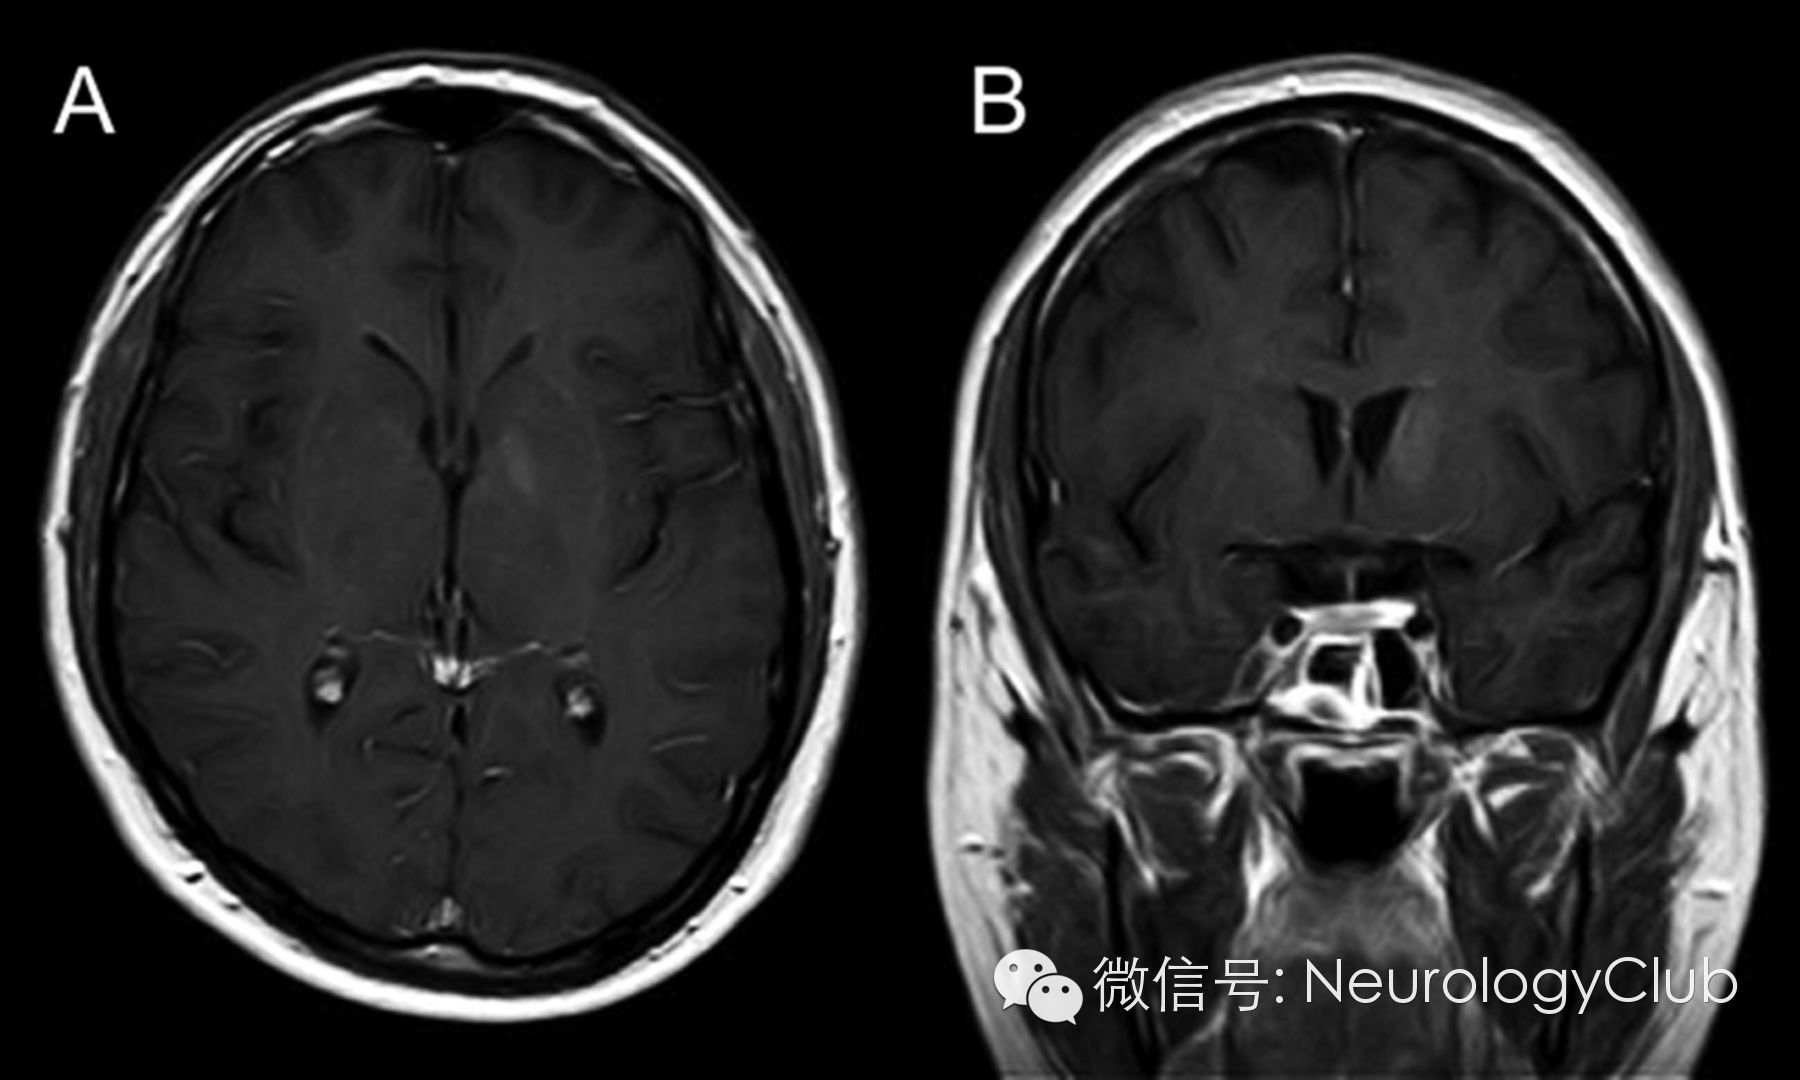

30岁男性,表现为面-臂肌张力障碍发作(faciobrachial dystonic seizures,FBDS)。发作期和发作间期的脑电图正常。脑脊液化验无殊。头颅MRI示左侧尾状核和苍白球强化病灶(图1)。血清LGI-1(富亮氨酸胶质瘤失活1蛋白)抗体阳性。全身CT扫描未发现恶性肿瘤。患者行5个周期的血浆置换后再接受长期的激素治疗,完全恢复。5月后复查头颅MRI,发现病灶强化信号减弱(图2)。LGI-1是一种与电压门控钾离子通道相关的分泌蛋白,在新皮质与海马区高度表达。LGI-1突变见于合并听觉症状的常染色体显性遗传颞叶癫痫(autosomal dominant partial epilepsy with auditory features,ADPEAF)。本例患者无ADPEAF的临床症状。关于FBDS是一种癫痫发作还是肌张力障碍仍存在争论。本例患者基底节区受累可与这一争议相关。

图2:治疗后复查增强MRI